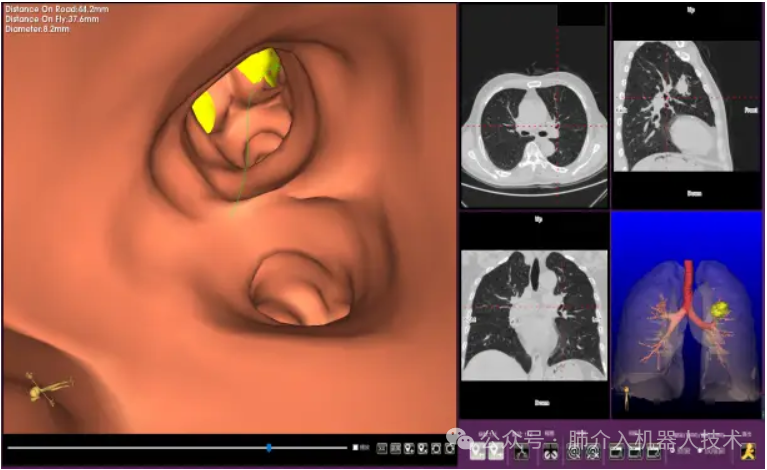

03、奧泰康助力肺部穿刺手術導航系統獲證

2024年1月31日,經國家藥品監督管理局公示,蘇州朗開醫療技術有限公司自主研發的肺部穿刺手術導航系統(國械注準20243010222)獲得NMPA批準上市,奧泰康助力本項目注冊申報服務,系2024年奧泰康助力獲得的首張三類醫療器械注冊證。

25、醫達健康IQQA®極星干將™2號Robot智能穿刺導航定位機器人獲批上市

2024年8月,由醫達健康自主創新研發的IQQA®極星干將™2號Robot智能穿刺導航定位機器人通過國家藥品監督管理局(NMPA)注冊審核,并獲得第三類醫療器械注冊證,奧泰康負責臨床試驗服務。